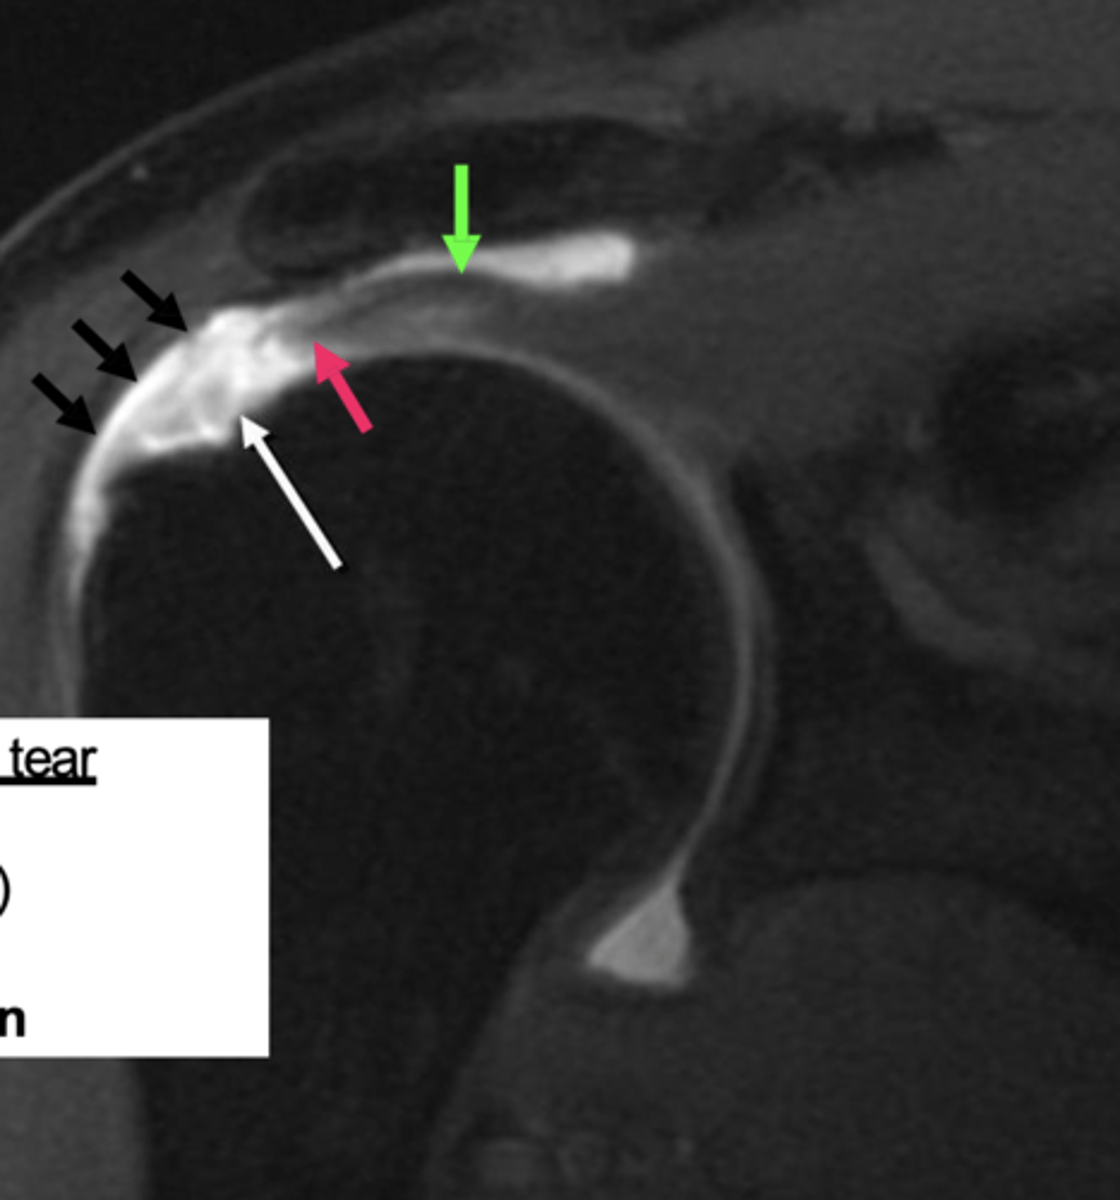

Full-thickness tear!!

- fluid (area of tear) in white

- retraction in red

- bucking in green

What is this image depicting w/ the rotator cuff? (hint: it is a T2 image)